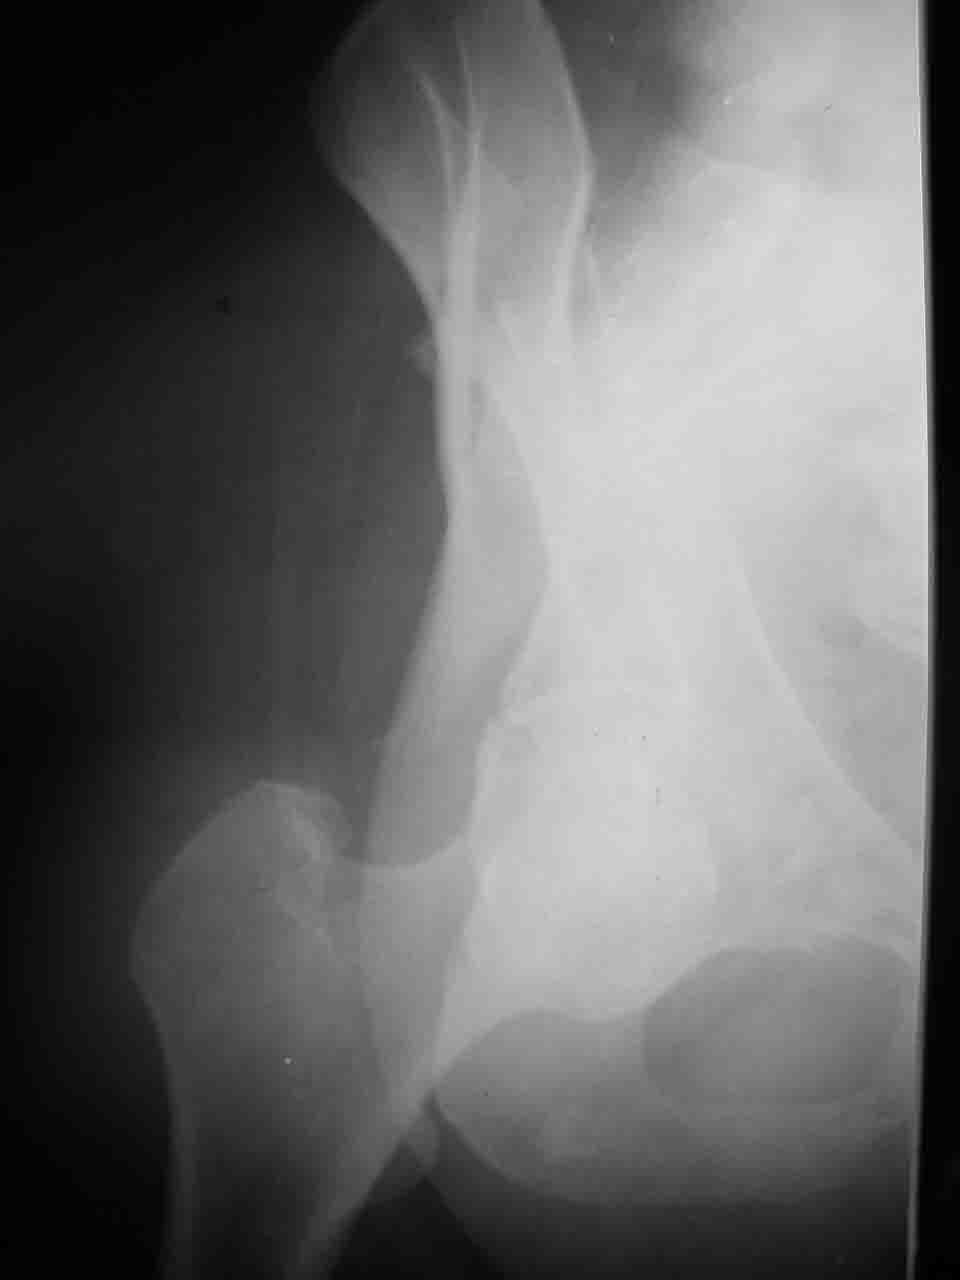

Комбинированные доступы - хорошая альтернатива, меньший процент осложнений, но я заметил , что без сбора *мозаики* безымянной кости сложно отрепонировать переднюю колонну, а с нерепонированной передней колонной невозможно анатомично собрать заднюю колонну и соотв. фрагменты стенки - так.что все равно открывать придется широко. Поэтому выбирая комбинированный

подход, передний доступ должен был бы быть продлен до задней трети крыла безымянной кости, а задний - практически до того же уровня, оставляя 6-7 см мостик. При этом вместо одного послеоп. рубца у больного остаются два сравнительно длинных.